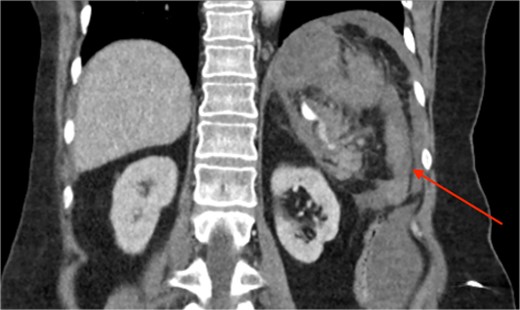

Triple-phase computed tomography (CT) of the abdomen and pelvis revealed a sizeable acute haematoma in the left upper abdomen, below the gastric fundus and body, alongside the pancreatic tail and splenic hilum, extending amongst the proximal small bowel mesentery and into the left subphrenic space. The origin of the haemorrhage appeared to arise from the left upper quadrant. There was a pseudoaneurysm in close proximity to the pancreatic tail and splenic hilum, apparently arising from the adjacent distal splenic artery. CT scan did show local contrast extravasation into the haematoma, as mentioned above (Figs 1–3).

CT angiography of the abdomen with 3D reconstruction. Ruptured SAP.